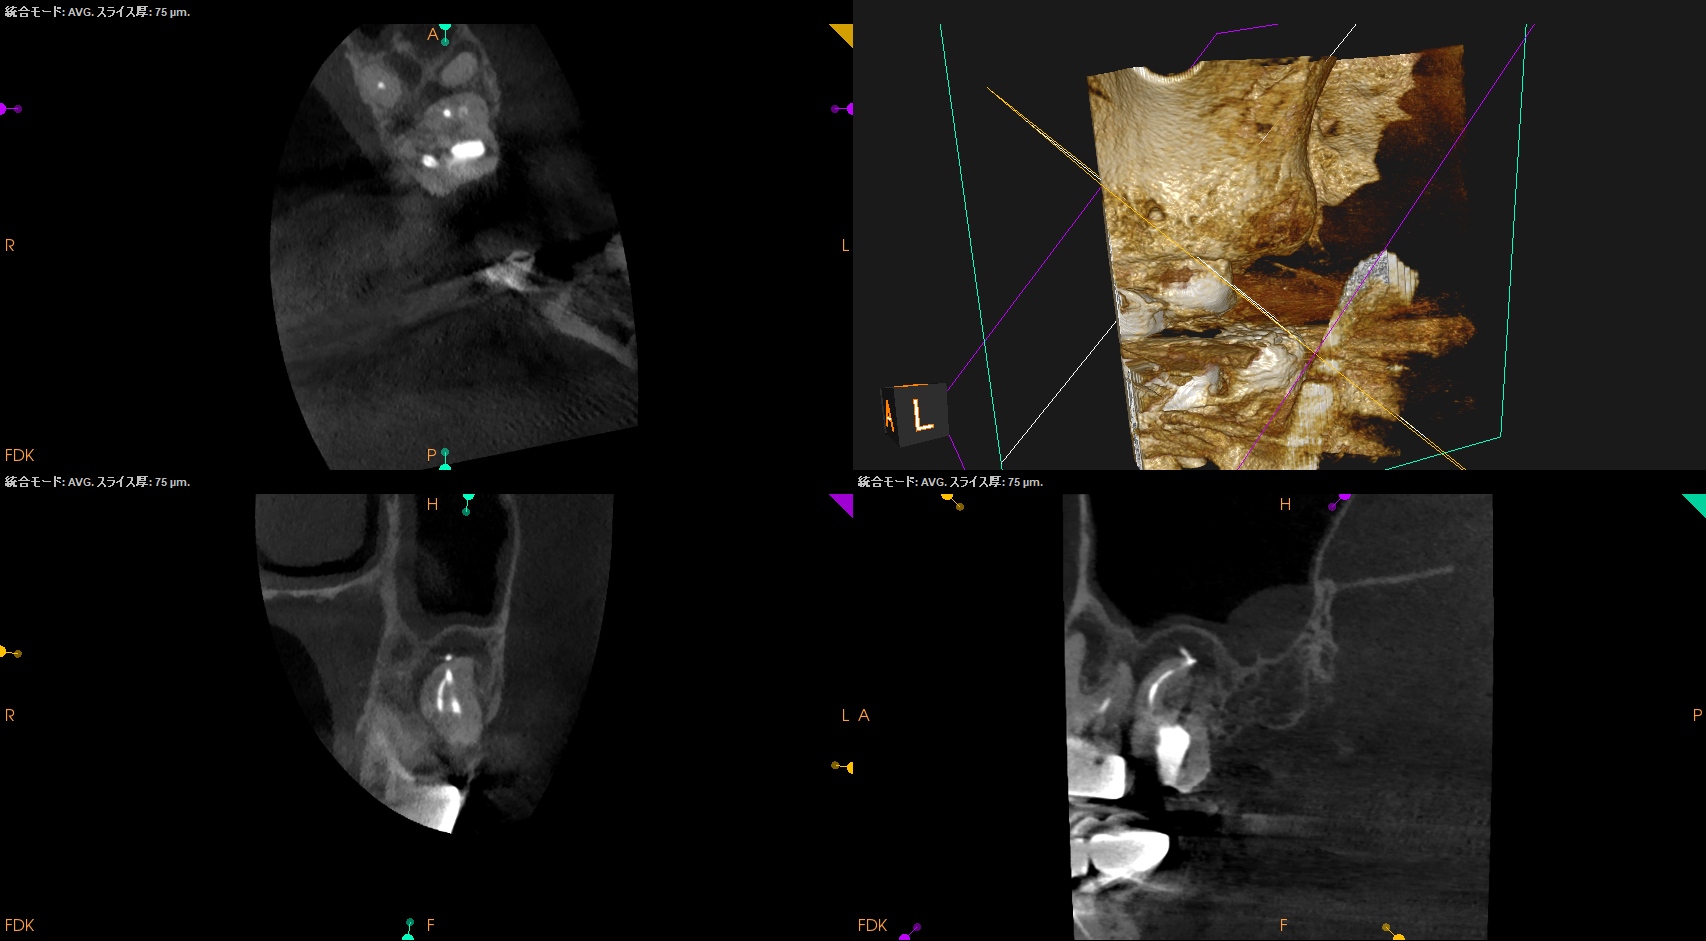

術後のPA, CBCTは以下である。

MB1

MB2

DB

P

問題はないだろう。